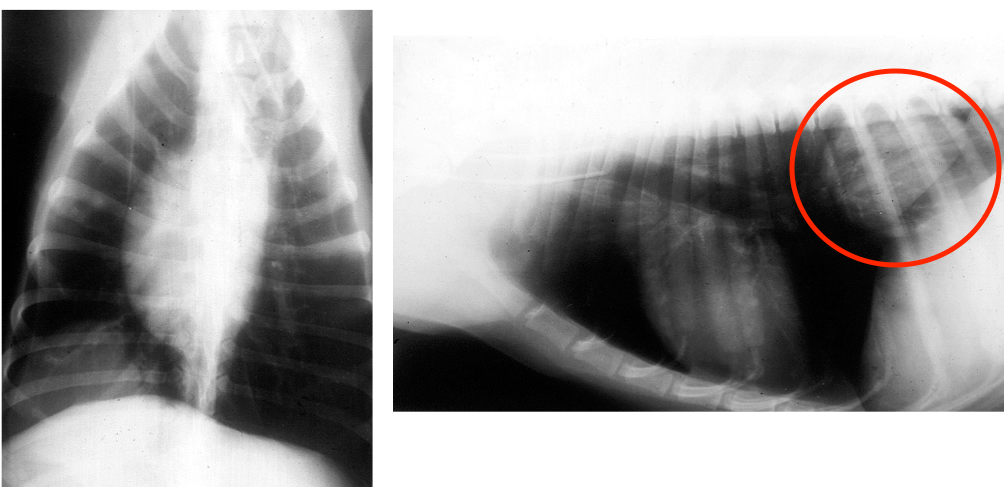

What finding is circled here?

A

Air bronchogram